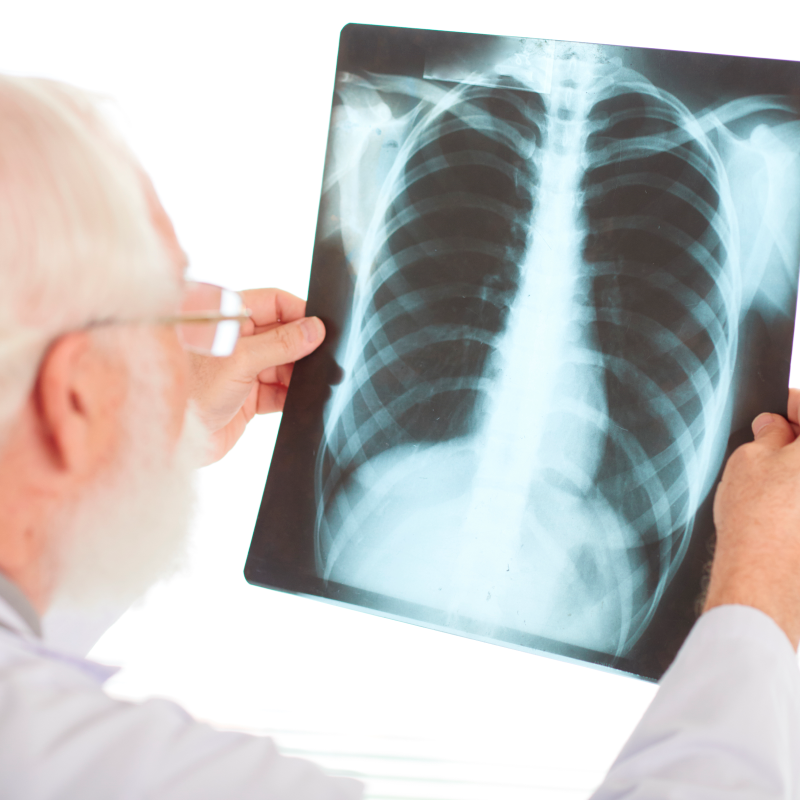

Para mejorar la experiencia de todos nuestros pacientes contamos con: Exámenes de Laboratorio, Rayos X, Ecografía y Farmacia.

Exámenes e Imágenes